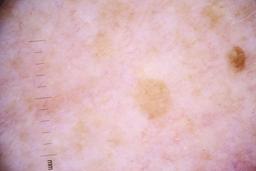

ISIC_4077341

Clinical

| Field | Value |

|---|---|

| acquisition_day | 1 |

| age_approx | 50 |

| anatom_site_1 | Trunk |

| anatom_site_2 | Anterior trunk |

| concomitant_biopsy | False |

| dermoscopic_type | contact non-polarized |

| diagnosis_1 | Benign |

| diagnosis_confirm_type | serial imaging showing no change |

| family_hx_mm | False |

| image_type | dermoscopic |

| lesion_id | IL_9238622 |

| patient_id | IP_1969685 |

| personal_hx_mm | True |

| sex | male |

Columns

Showing first 50 images.